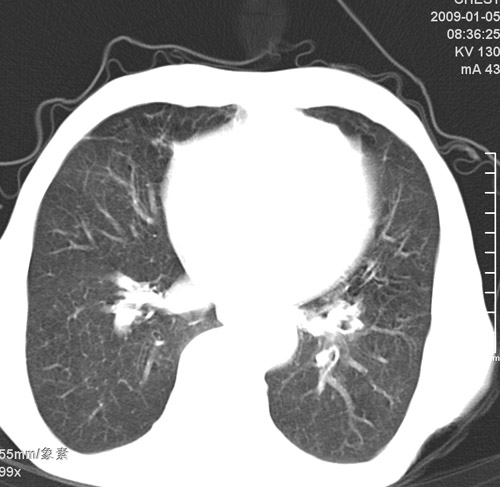

标题: CT17529:男 76 胸背部不适半月 胸透支气管炎 行CT检查 [打印本页]

标题: CT17529:男 76 胸背部不适半月 胸透支气管炎 行CT检查

意见 老年肺 少许炎症 肺大泡 右肺门略大 但支气管通畅  请各位高手指教如何下意见

间质纤维化伴少许炎症!另:肺大泡形成!

支持楼主意见,右肺门略大,可能为肺动脉增粗.

慢支肺气肿,肺动脉高压.